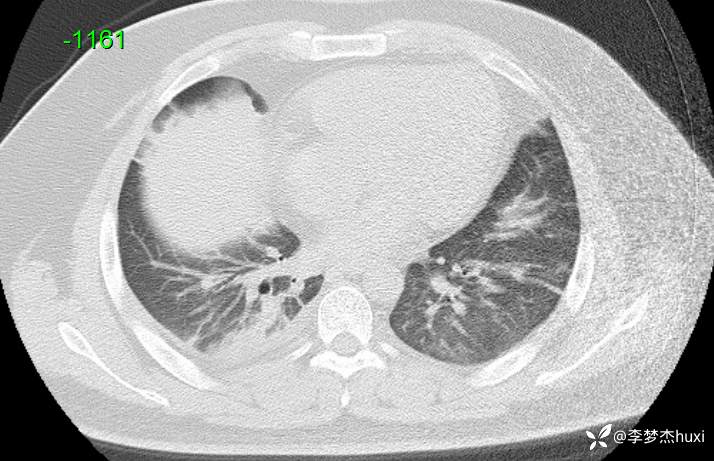

【现病史及既往史】: 1.患者青年 男,患者缘于2天前无诱因出现胸痛,为前胸痛,伴后背疼痛,咳嗽及深呼吸时明显,伴咳嗽,痰不易咳出,伴恶心、呕吐,伴发热,体温最高达37.7℃,无寒战,无咯血,院外未应用药物治疗,症状无明显好转,为求进一步治疗来院就诊,门诊查胸部CT提示:双肺炎症,较前进展,双肺纹理增重,右肺实性结节,建议随诊复查,双侧胸膜局部增厚,右侧胸腔少量积液。以“肺炎”收住院;。

【检查】: 4.辅助检查:心电图示:窦性心动过速,门诊查胸部CT提示:双肺炎症,较前进展,双肺纹理增重,右肺实性结节,建议随诊复查,双侧胸膜局部增厚,右侧胸腔少量积液。

【临床诊断】: 社区获得性肺炎,非重症。